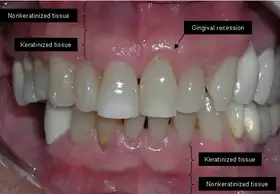

The soft tissue in the oral cavity is classified as either keratinized or nonkeratinized based on the presence of keratin in the epithelium.[4] In health, the soft tissue immediately around the teeth is keratinized and is referred to as keratinized tissue or gingiva. Alveolar mucosa is non keratinized oral epithelium and is located apical to the keratinized tissue, delineated by the mucogingival junction (MGJ). It should also be pointed out that mucosa can surround a tooth in health.[5] Nonkeratinized tissue also lines the cheeks (buccal mucosa), underside of the tongue and floor of the mouth. The lips contain both non-keratinized tissue (on the inside) and keratinized tissue on the outside, demarcated by the vermillion border. The dorsum of the tongue is keratinized and features many papillae, some of which contain taste buds.[6]